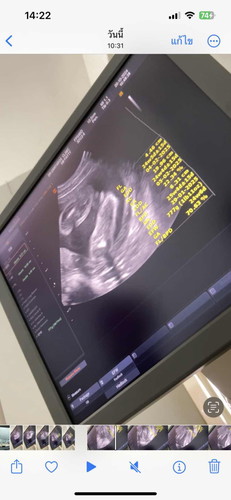

แม่ๆ ช่วยดูหน่อยค่ะอายุครรภ์ 24 สัปดาห์ แบบนี้ใช่ลูกสาว100%ไหมคะหมอบอกว่าน้องนอนท่าก้นแอบดูยาก หมอเดาว่าลูกสาวแต่ไม่แน่ใจ

น่าจะผู้หญิงนะค่ะเป็นรูปแฮมเบอร์เกอร์ ถ้าผู้ชายจะเหมือนหนองไก่ หนูฟังที่หมอบอกเตียงข้างๆมา 🤣🤣

อยู่ท่านี้ดูยากจริงค่ะ บางมุมดูเป็นกลีบ แต่บางทีก็เหมือนจะไข่แค่ไม่เห็นจู๋

แบบนี้ใช่แคมน้องไหมคะแม่ ช่วยดูทีคะ

ผู้หญิงนะคะ ไม่เห็นกระจู๋น้อง